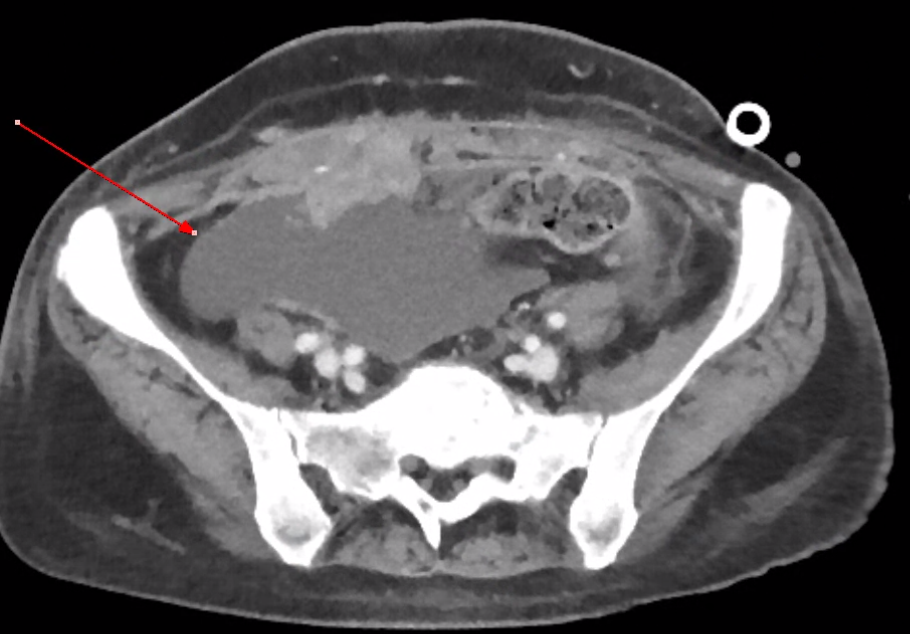

| 수술 후 액체 저류 (Post operative fluid collection) (0) | 2024.03.31 |